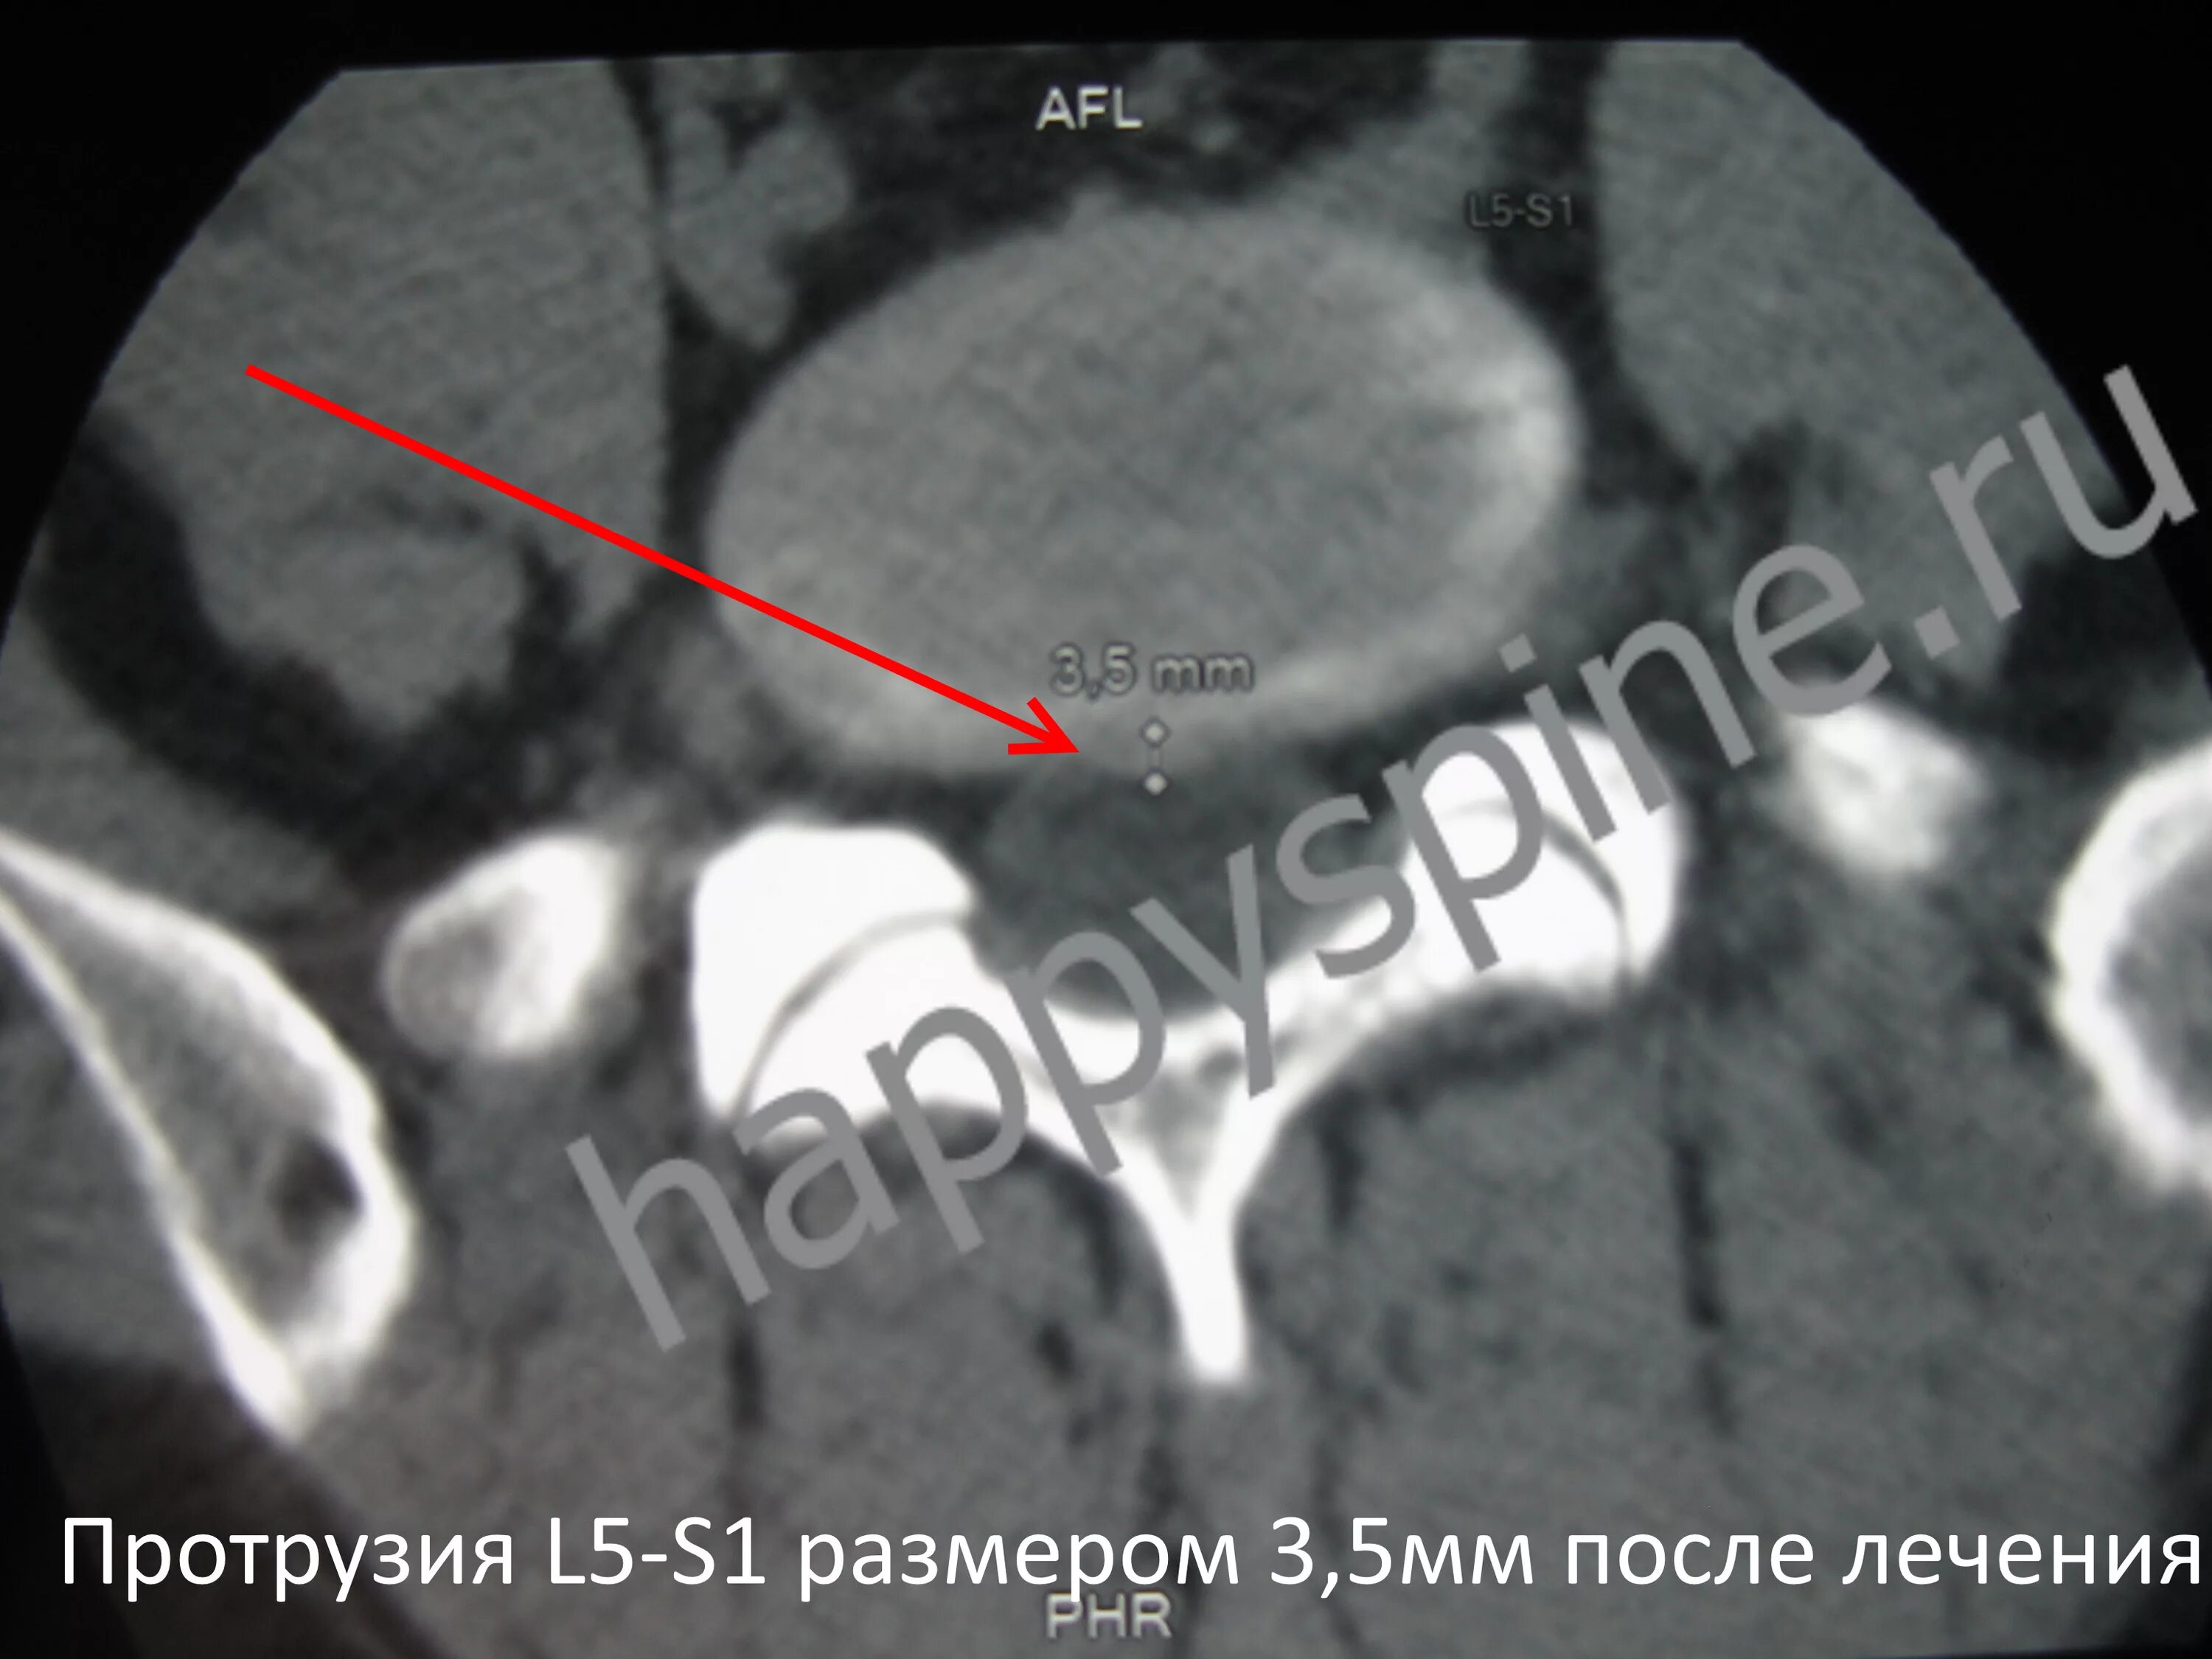

Протрузия дисков 4 5